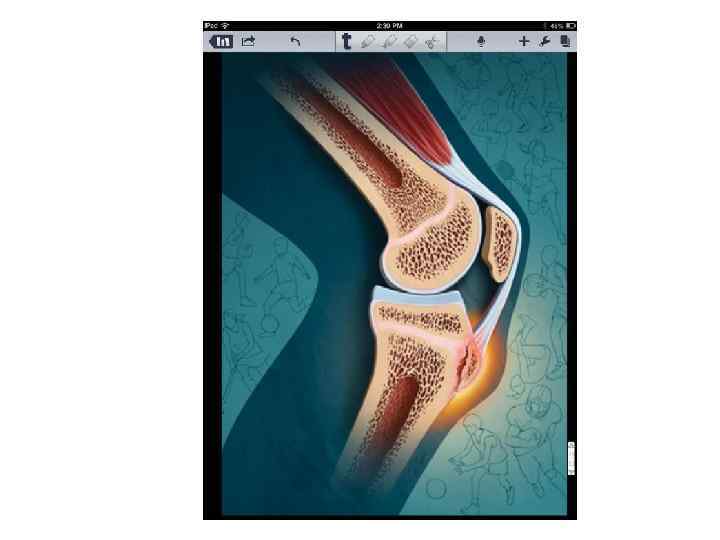

Коленный сустав • «Рентгеновская суставная щель» этого сустава является самой широкой во всей костно-суставной системе человека, так как она соответствует кроме истинной суставной щели и суставных хрящей еще и хрящевым менискам.

Коленный сустав • «Рентгеновская суставная щель» этого сустава является самой широкой во всей костно-суставной системе человека, так как она соответствует кроме истинной суставной щели и суставных хрящей еще и хрящевым менискам.

КОЛЕННЫЙ И МЕЖБЕРЦОВЫЙ СУСТАВЫ - т. о в дист. эпифизе бедр. и прокс. эпифизе бберцовой костей - 9 мес внутриутробно (должен быть у доношенного новорожденного) - т. о. в надколеннике и головке мберцовой кости - 3, 5 - 4, 5 года - т. о в бугристости бберц. к. - 9 лет, син – 15 -17 лет - синост-ие метаэпифизарных ростковых зон бедренной и большеберцовой костей – 15 -17 лет

КОЛЕННЫЙ И МЕЖБЕРЦОВЫЙ СУСТАВЫ - т. о в дист. эпифизе бедр. и прокс. эпифизе бберцовой костей - 9 мес внутриутробно (должен быть у доношенного новорожденного) - т. о. в надколеннике и головке мберцовой кости - 3, 5 - 4, 5 года - т. о в бугристости бберц. к. - 9 лет, син – 15 -17 лет - синост-ие метаэпифизарных ростковых зон бедренной и большеберцовой костей – 15 -17 лет